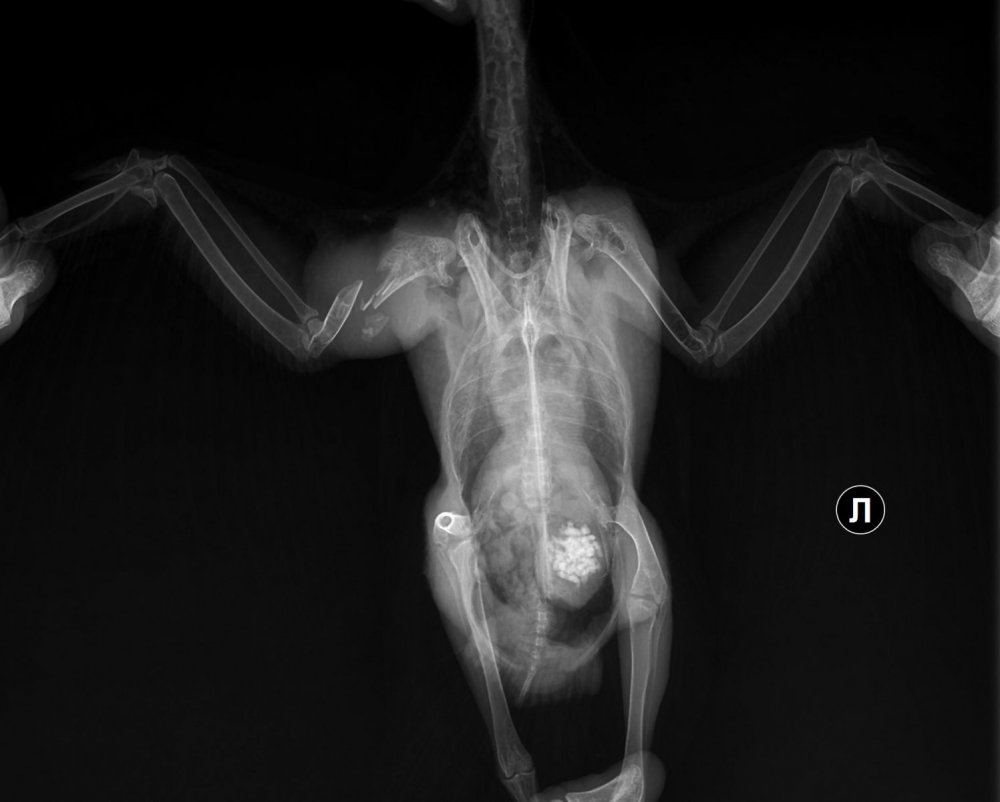

Рентген №1 - 08.121_3011977922r.thumb.jpg.1c03db7fd202f6f6e764bf55e9a4103d.jpg

1_3011977922r.thumb.jpg.1c03db7fd202f6f6e764bf55e9a4103d.jpg1_3011993622r.thumb.jpg.7575556377acddc5708415dfcdcf6558.jpg

Рентген контрольный - 22.12

1_3131795322r.thumb.jpg.d84909cef2a8ef1a6f8861285e32d1be.jpg1_3131813522r.thumb.jpg.2b83701bfbf4fd71082afc4022d192bd.jpg

Врач после второго рентгена говорила, что надежда ещё не потеряна, но скорее нет чем да, а если полетит, то не раньше чем через месяц. Прошло уже два, прогресс крайне мал (

Если представленные снимки свежие- то летать он не будет, т.к. за 3 месяца после аварии у него нет даже признаков консолидации или хотя бы образования ложного сустава.

на представленных снимках перелом полный , с чрезвычайно большим смещением всех отломков.  Если не производилась хоть какая-то репозиция отломков, то там нечему и некуда прирастать... там расстояние между частями отломков долее 5 мм, а то и все 8.

Снимки датированы - 08.12.22; 22.12.22